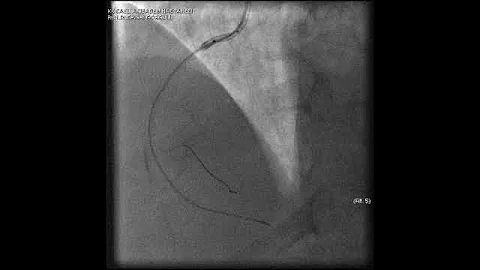

Complex Pci For Rca Cto With Bifurcation At Distal Cap Video 7